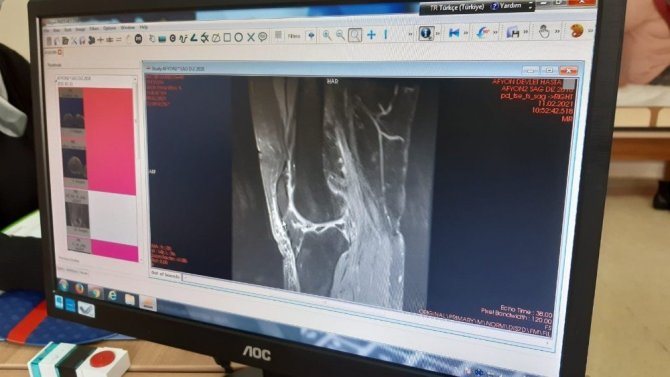

Afyonkarahisar kent merkezinde kar kalınlığının 20 santimetreye ulaşmasıyla birlikte kayganlaşan zeminlerde düşmeye bağlı kırıklarda artış gözlendi. Afyonkarahisar Devlet Hastanesi Ortopedi ve Travmatoloji Uzmanı Dr. Aykut Özdemir, son bir haftadır düşmeye bağlı olarak kırık vakalarında artış olduğunu belirtti. Son günlerde yaşlı hastalarda düşmeye bağlı kırık şikayetlerinin arttığını kaydeden Özdemir, "Özellikle son bir haftadır hava şartlarındaki olumsuzluk sebebiyle karlanma, buzlanma çok arttı. Bu nedenle özellikle yaşlı hastalarımızda kalça kırıkları, el ve ayak kırıklarında çok fazla artış oldu vakalarımızda. Özellikle bu havalarda yaşlı hastalarımızın evden çıkmamasını öneriyorum. Özellikle kalça kırıkları bizim için yaşlı hastalarda sıkıntı teşkil ediyor" diye konuştu.

Yaşlıların karlı ve buzlu havalarda evinden çıkmaması gerektiğini vurgulayan Özdemir, özellikle kalça çıkıklarının ölümle dahi sonuçlandığını söyledi. Özdemir, "Karlanma ve buzlanma Afyon'da çok fazla. Özellikle akşam vakitlerinde ve gündüz sabah erken vakitlerde yaşlı hastaların dışarı çıkmamalarını öneriyorum. Hele ki bu Covid döneminde teması azaltmak babında ve travmayı azaltmak anlamında evden çıkmamalarını öneriyorum. Ev içindeki kazalarda da oda eşiklerine, banyo eşiklerinden atlarken çok dikkatli olmalarını öneriyorum. Çünkü kalça kırıkları el bileği kırıkları, ayak bileği kırıkları gibi değil hastada ölüm ve ek hastalık risklerini arttırdığı için bizim için ve hasta için çok önemli oluyor. Bu dönemde mümkünse evden çıkmasınlar" dedi.